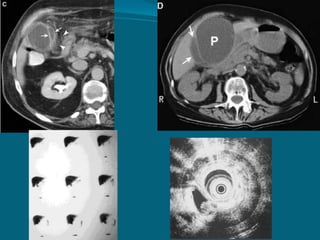

VESICULA BILIAR CON COLECISTITIS

CRONICA, COLELITIASIS

Y UN PEQUEÑO TUMOR PAPILAR A NIVEL DEL

CONDUCTO CISTICO (macro)

Adenocarcinoma Papilar de la Vesícula Biliar

(micro)

VESICULA BILIAR CONCOLECISTITIS CRONICA, COLELITIASIS Y UN PEQUEÑO TUMOR PAPILAR A NIVEL DEL CONDUCTO CISTICO (macro) Adenocarcinoma Papilar de la Vesícula Biliar (micro)